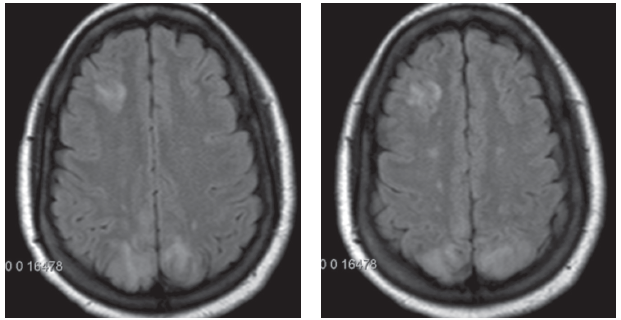

Carlito Arenas, Jr., MD; Vincent Bryan Salvador, MD; Sabaa Joad, MD; Arunakumari Penumadu, MD; Valeriy Vilensky, MD

A 25-year-old African American, G2P2, without prior known comorbidities presented to the emergency department with 2 episodes of seizures, 8 days after an uncomplicated full-term normal spontaneous vaginal...